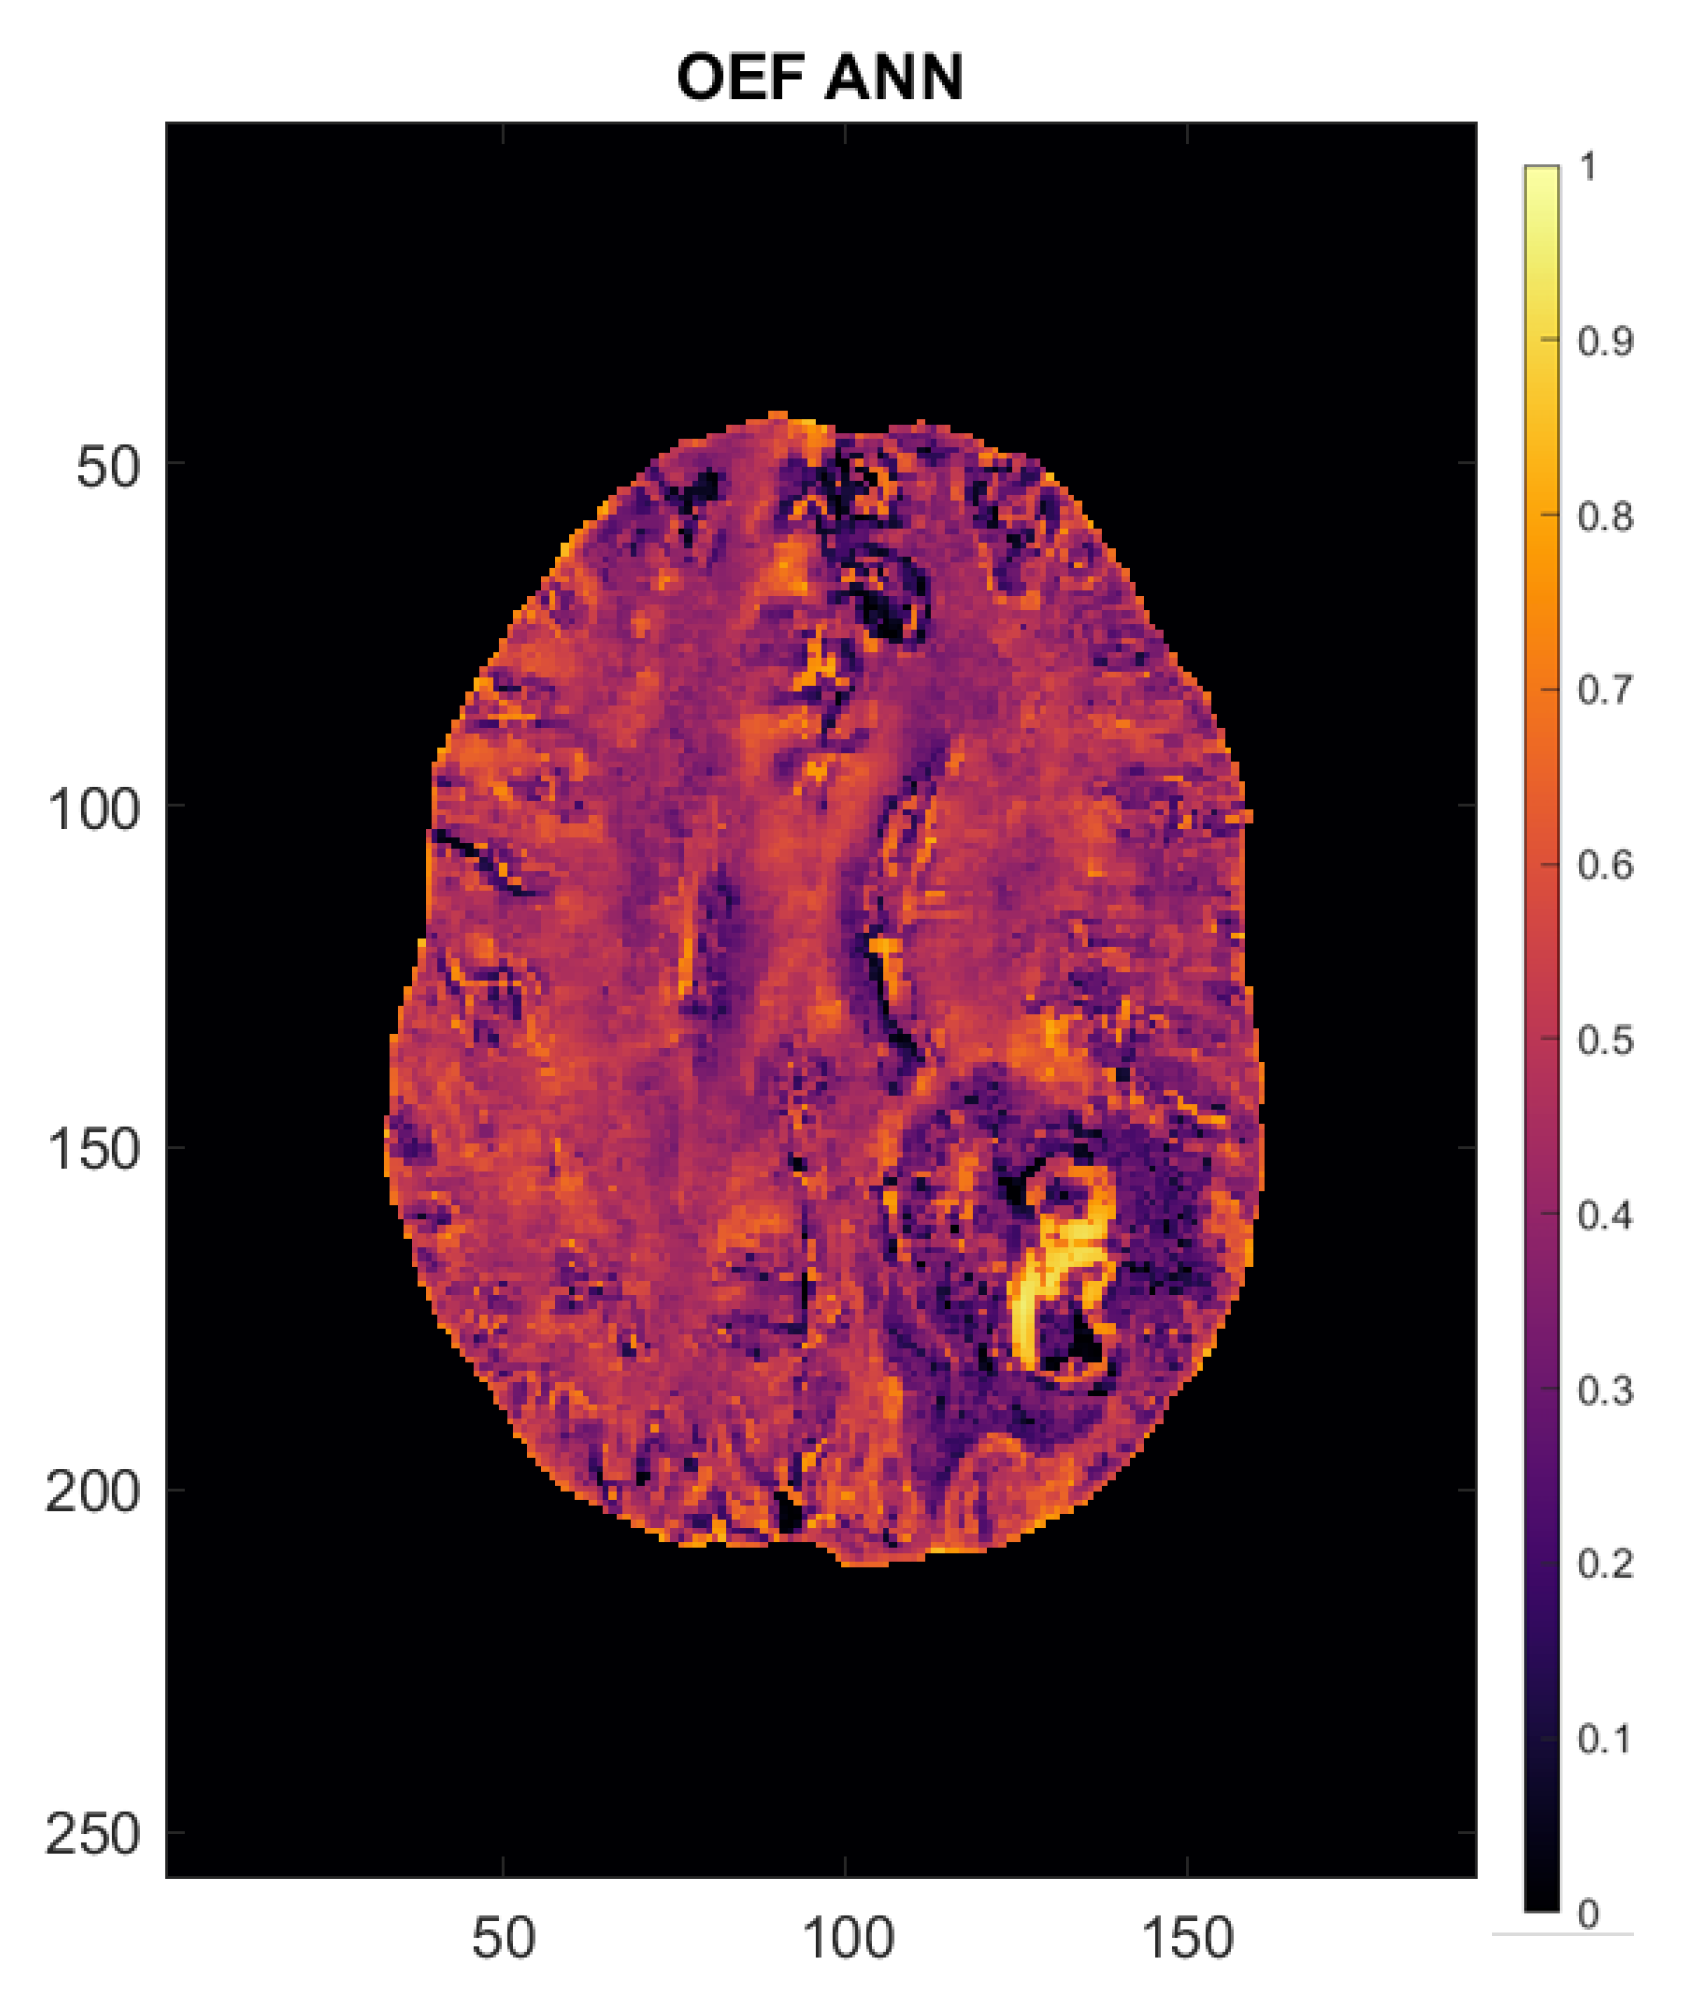

2.4. Calculation of Perfusion and Oxygenation Parameters

2.5. Artificial Neural Network

- Hubertus, S.; Thomas, S.; Cho, J.; Zhang, S.; Wang, Y.; Schad, L.R. Using an artificial neural network for fast mapping of the oxygen extraction fraction with combined QSM and quantitative BOLD. Magn. Reson. Med. 2019, 82, 2199–2211. [Google Scholar] [CrossRef]